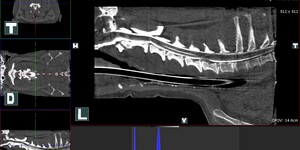

- zobrazovací diagnostika : sonografie, echokardiografie, endoskopie rigidní, flexibilní,digitální rtg

- neurologie, neurochirurgie